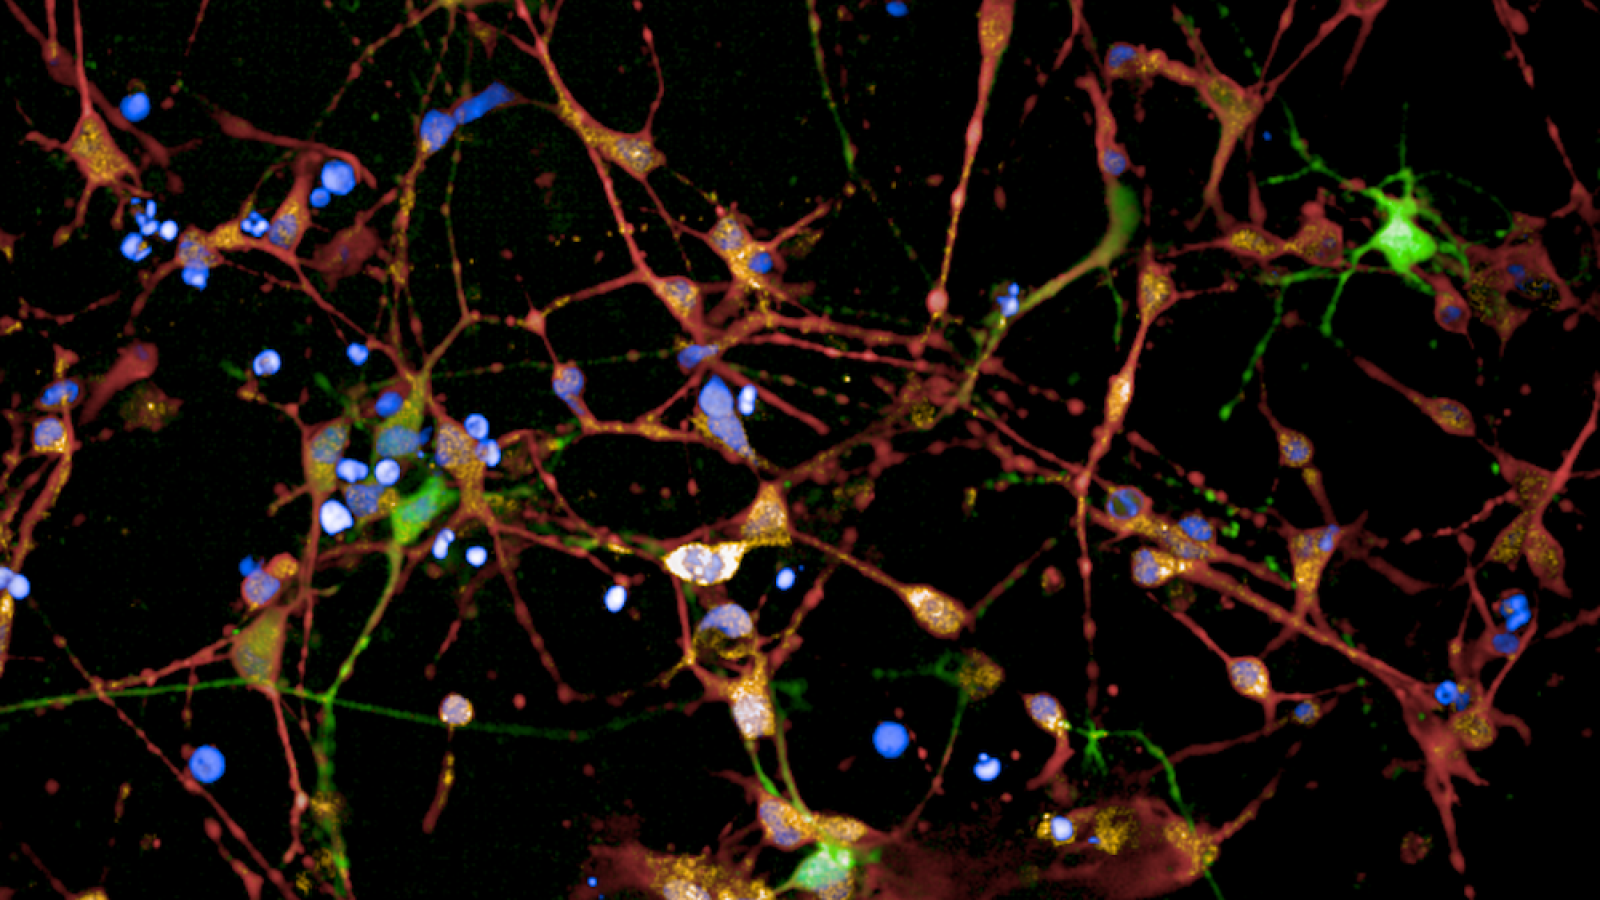

Huntington's patient brain cells

Fluorescence to label different cells and structures of a brain

Banner image: Immunofluorescent staining of HD patient 125 CAG iPSC-derived striatal neuron cultures following 36 days of differentiation. Credit: Figure adapted/reproduced with permission from Bunting EL, Donaldson J, et al., Antisense oligonucleotide-mediated MSH3 suppression reduces somatic CAG repeat expansion in Huntington's patient iPSC-derived striatal neurons, Science Translational Medicine, 2025.